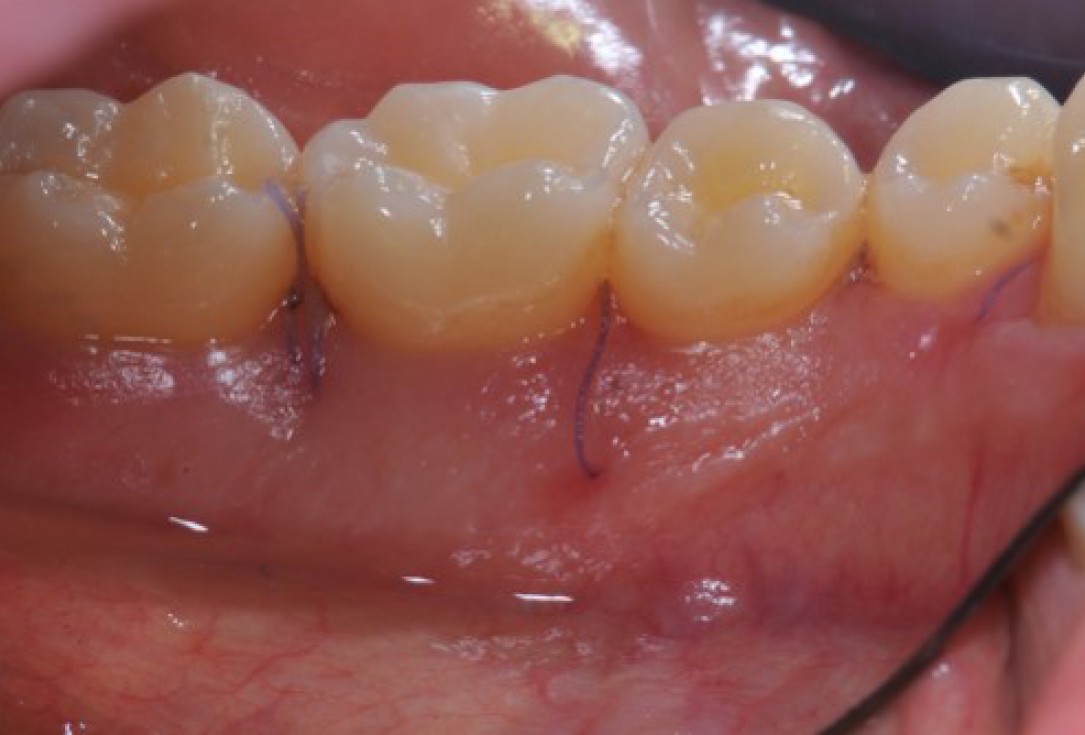

11/22 - Coronal advancement of the flap and suturing to achieve primary wound closure. Buccal view.

Deep intrabony defects treated using Straumann® Emdogain® - Dr. M. Stefanini